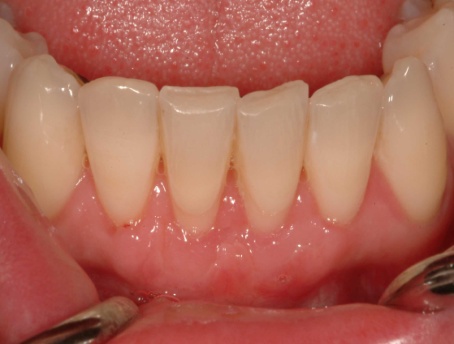

Recession on two lower incisors